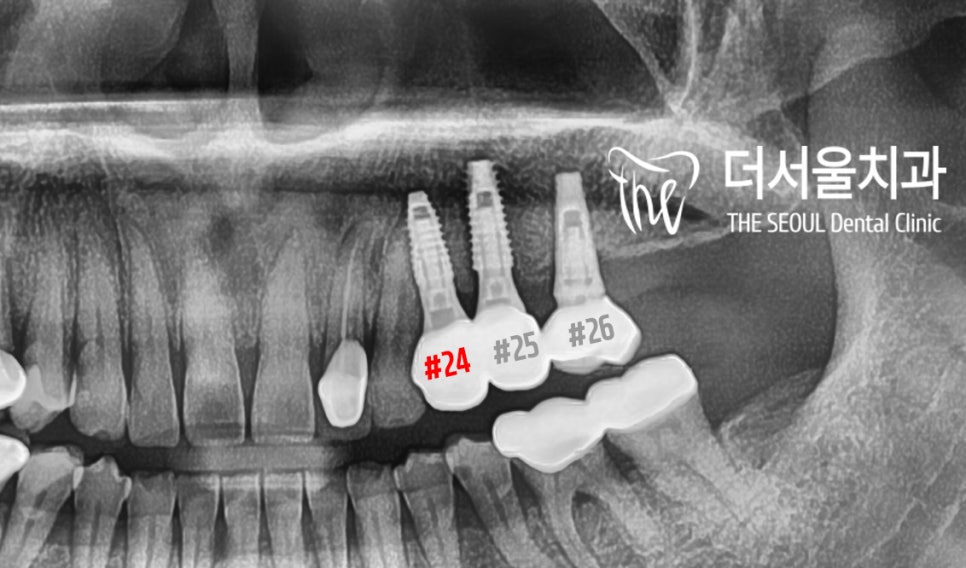

치근단 사진을 찍어 확인해 봤더니

표시 해둔 주변으로 염증이 생겨

골퇴축(bone defect)이 일어나 있네요.

다행히 뼈가 많이 상한 것에 비해

골융합도 안정적으로 이루어졌으며

원하는 방향대로 심어진 모습이네요.